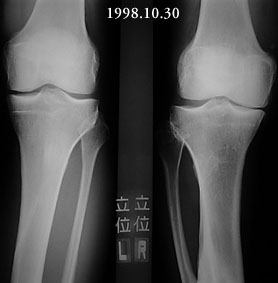

I am a 55-year-old male who suffered a compound fracture of the right tibia and fibula and extensive soft tissue damage, including vascular damage, from the impact of an automobile pinning the leg to a concrete wall in 1971. This occurred while I was a pedestrian. Emergency surgery restored circulation and set the tibia and fibula fragments with no internal fixation (due to concern about infection) and plaster cast immobilization. Later a bone graft was performed, and after physical therapy an apparently full recovery occurred, except a slight varus deformity, reduced vascularity, and reduced range of motion in the ankle. Over the years, the varus deformity worsened to 22 degrees and led to moderate osteoarthritis. To correct the deformity and straighten the tibia, an open-wedge osteotomy was performed in November 1999, with a bone graft from the other iliac crest. Plate fixation was used, as the bone was too hard to ream, so it was impossible to insert a pin. I have used the Exogen ultra-sound device every day since the surgery. Gradual improvement led to enhanced weight-bearing ability, and I have been walking with a cane since April 2000. Although X-rays taken June 16 showed no deformity, the varus deformity has recurred in the October 16 X-rays.

I am sending standing X-ray images of both knees for posting to the website. They show moderate osteoarthritis in the right knee and normal cartilage in the left knee. Knee pain was my initial complaint, and it was eventually diagnosed as resulting from the uneven pressure on the joint caused by the varus deformity. As to why the mild varus deformity of 1971 progressed to a 22-degree deformity in 1998, one answer I have received is that the 1971 fracture never healed properly.